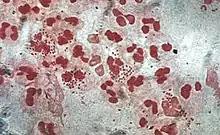

Monocytes develop in the bone marrow and reach maturity in the blood. Mature monocytes have large, smooth, lobed nuclei and abundant cytoplasm that contains granules. Monocytes ingest foreign or dangerous substances and present antigens to other cells of the immune system. Monocytes form two groups: a circulating group and a marginal group that remain in other tissues (approximately 70% are in the marginal group). Most monocytes leave the blood stream after 20–40 hours to travel to tissues and organs and in doing so transform into macrophages[70] or dendritic cells depending on the signals they receive.[71] There are about 500 million monocytes in one litre of human blood.[5]

Neutrophils are normally found in the bloodstream and are the most abundant type of phagocyte, constituting 50% to 60% of the total circulating white blood cells.[79] One litre of human blood contains about five billion neutrophils,[5] which are about 10 micrometers in diameter[80] and live for only about five days.[40] Once they have received the appropriate signals, it takes them about thirty minutes to leave the blood and reach the site of an infection.[81] They are ferocious eaters and rapidly engulf invaders coated with antibodies and complement, and damaged cells or cellular debris. Neutrophils do not return to the blood; they turn into pus cells and die.[81] Mature neutrophils are smaller than monocytes and have a segmented nucleus with several sections; each section is connected by chromatin filaments—neutrophils can have 2–5 segments. Neutrophils do not normally exit the bone marrow until maturity but during an infection neutrophil precursors called metamyelocytes, myelocytes and promyelocytes are released.[82]